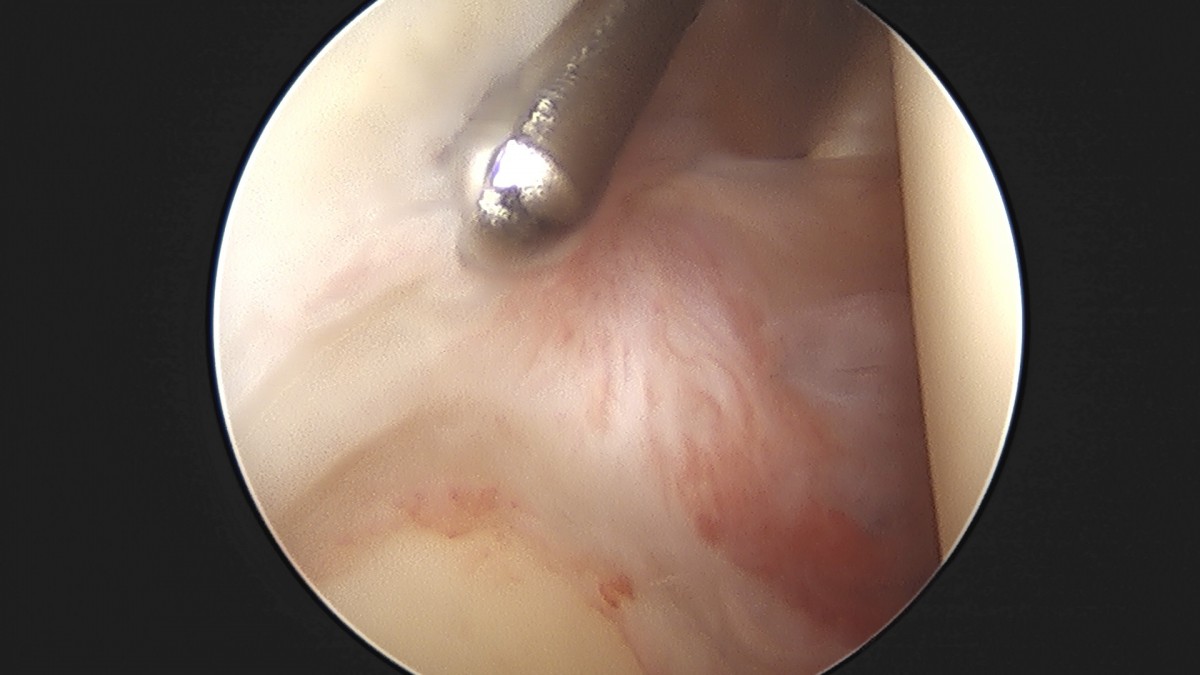

이재상원장님 어깨 석회 제거술 조광O 환자

dae765e4d9ac96aee867c9d6292d8784_1758004691_9404.jpg